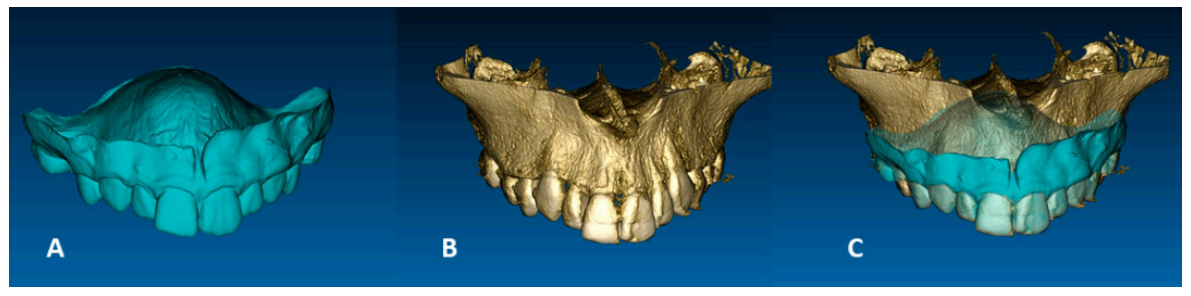

The impression of patient dental arches was taken with alginate material, stone models were poured and then scanned with Aton scanner (88Dent, Pero, Italy) to obtain a virtual model. Alternatively, the 3D digital model of dental arches can be directly generated with the use of an intra-oral scanner [10]. Then a Cone Beam Computed Tomography (CBCT) exam of the patient maxilla with a Field of View (FOV) of 5 × 8 cm2 was obtained with a Carestream CS 8100 3D machine (Carestream Dental LLC., Atlanta, GA, USA). The Real Guide software (3Diemme, Figino Serenza, Italy) was used to align the virtual model of the dental arches with the CBCT image through a best-fit automatic algorithm in order to create an integrated model (Figure 3) on which the DIVA appliance was subsequently virtually designed.

Figure 3.

Alignment between virtual model of maxillary dental arch (A) and virtual model of the maxilla cone beam computed tomography (CBCT) (B) to create the integrated model (C).